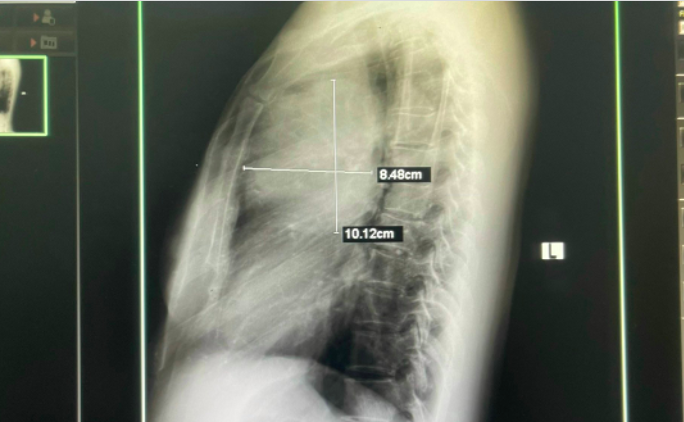

Sau khi được các bác sĩ thăm khám và chỉ định cận lâm sàng, kết quả hình ảnh chụp X-quang tim phổi cho thấy người bệnh có khối u phổi trái, kích thước 8,48cm x 10,12cm. Ngay lập tức, người bệnh được các bác sĩ tư vấn chuyển lên tuyến trên thực hiện các kỹ thuật chẩn đoán chuyên sâu. Kết quả bác sĩ chẩn đoán anh H. mắc ung thư phổi.

Bác sĩ chuyên khoa I Trần Thị Hồng Vân, Trưởng Phòng khám đa khoa, Trung tâm Kiểm soát bệnh tật tỉnh Phú Thọ, cho biết chụp X-quang tim phổi thường quy là phương pháp đơn giản, rẻ tiền và dễ thực hiện. Trên phim X-quang thường quy có thể phát hiện các tổn thương khối u có kích nhỏ dạng nốt đơn độc với kích thước 1 cm.